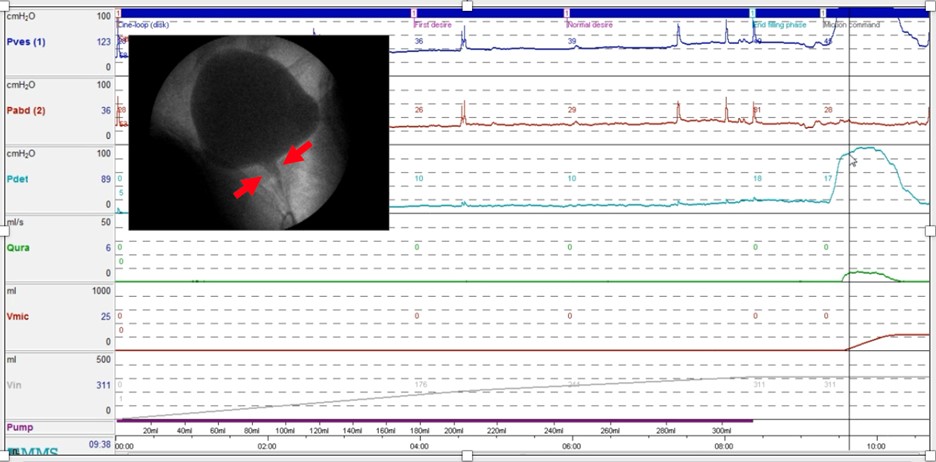

The current International Continence Society definition requires an ‘intermittent and/or fluctuating flow’ in the absence of a neurological condition (ICS Glossary). However, fluctuating flow is not universal leaving the rest without a diagnosis (Figure 1).

Figure 1: Video-urodynamics in an adult woman with refractory voiding difficulty and no anatomical narrowing showing high voiding pressure, slow (but steady rather than staccato) flow and a dilated proximal urethra (RED arrows) in the absence of any underlying neurological conditions on detailed neurological evaluation.